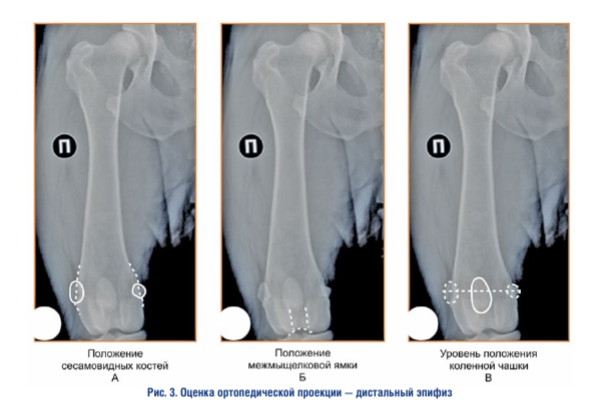

Оценка ортопедической проекции — дистальный эпифиз. При интерпретации правильной ориентации дистального эпифиза бедренной кости во фронтальной плоскости необходимо учитывать усредненную совокупность признаков, каждый из которых по отдельности не является абсолютным критерием адекватности проекции (рис. 3)

Положение сесамовидных костей. Сесамовид- ные кости должны быть разделены кортикальными слоями пополам. Сесамовидные кости являются структурой, которая относится к бедренной кости, но не принадлежит ей, поэтому, например, при изменении формы сесамовидных костей, при наличии остеоартрита сезамо-бедренных суставов, данный критерий может не отражать истинного положения дистального эпифиза бедренной кости.

Положение межмыщелковой ямки и контуров мыщелков. Межмыщелковая ямка должна иметь форму равномерно вогнутой окружности. Контуры латерального и медиального мыщелков должны хорошо визуализироваться, быть прямыми и располагаться посередине относительно ширины дистального эпифиза.

Положение коленной чашки. Коленная чашка должна находиться в своем нейтральном положении относительно блока коленной чашки на линии, соединяющей сесамовидные кости, и делить коленную чашку на примерно равные верхнюю и нижнюю части. Такая ориентация коленной чашки свидетельствует о параллельном положения бедренной кости относительно рентгеновской кассеты (фронтальной плоскости).

В тех случаях, когда выполняется рентгенография бедренной кости пациенту, у которого присутствует не вправляемый латеральный или медиальный вывих коленной чашки, и она располагается за пределами своего блока, необходимо ориентироваться только на линию, проведенную между сесамовидными костями.